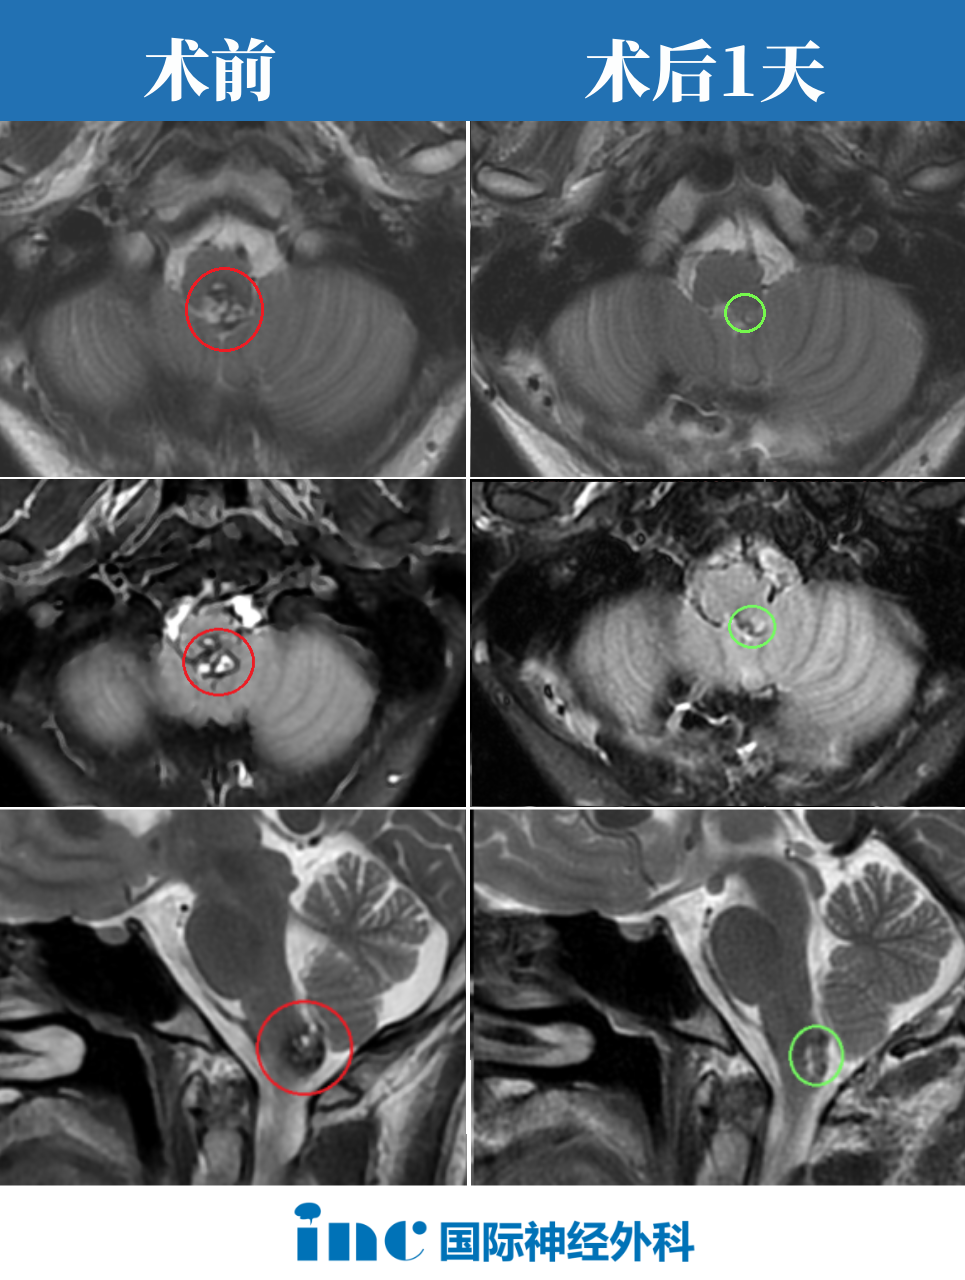

患者阿朔,19岁男性,大学生,确诊为脑干延髓海绵状血管瘤。发病前身体状况良好,热爱生活,具有积极向上的精神状态。疾病确诊时,医疗团队告知手术存在术后瘫痪和生活不能自理的风险,患者及家属陷入深度焦虑。

手术于2022年11月27日实施,全程进行手术直播。术中在神经电生理监测下,巴特朗菲教授成功完成肿瘤全切手术,操作精准有序。患者术后苏醒迅速,在ICU期间即恢复基本沟通能力,能够使用手机与家人联系。

术后第三天患者开始尝试下床行走,首次站立时感受到明显的功能恢复迹象。术后一个半月内,患者每日都能感知到身体功能的渐进性改善,这种积极的恢复趋势为患者提供了持续的心理支持。